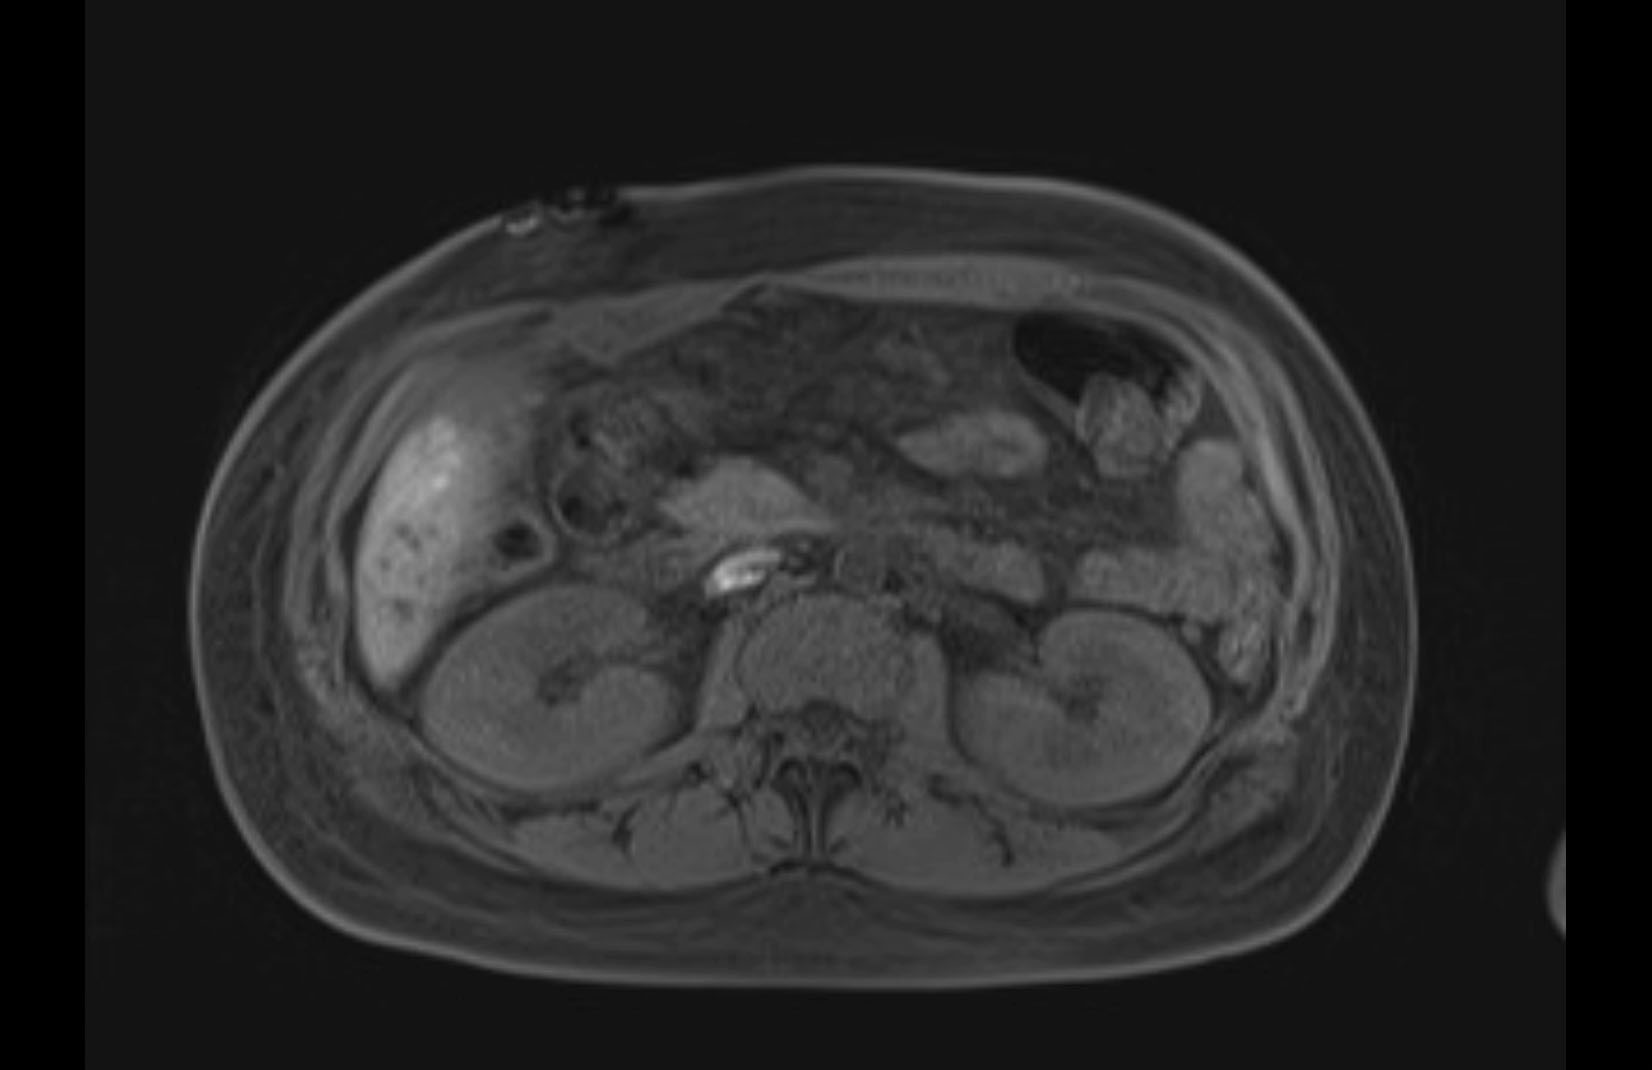

MRI T1

MRI T2

Imaging analysis

Based on initial findings, which issue(s) would you be most concerned about?